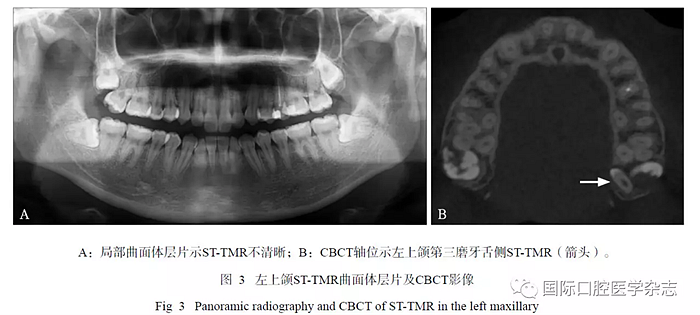

16例ST-TMR患者的CBCT顯示:21顆STTMR中埋伏阻生者占多數(shù)(18/21),3顆萌出(3/21);18顆埋伏阻生ST-TMR多數(shù)與第三磨牙同時(shí)阻生(10/18);萌出者2顆位于第三磨牙頰側(cè),1顆位于其方。ST-TMR位于第三磨牙遠(yuǎn)中較多(9/21),其余分布在第三磨牙的周?chē)易兓^大,如第三磨牙近中、頰(舌)側(cè)、根(冠)方;5顆ST-TMR緊鄰上頜竇底壁,1顆進(jìn)入翼上頜裂。位于腭側(cè)ST-TMR的CBCT較曲面體層片顯示更清晰(圖3)。